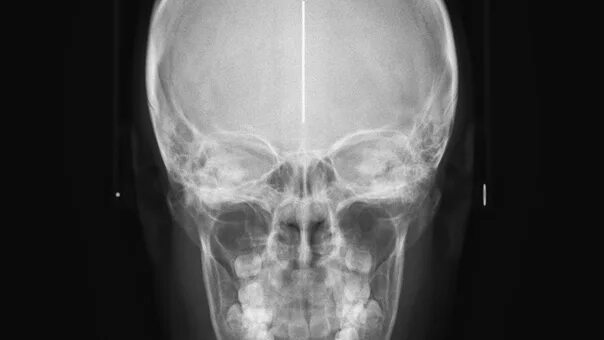

Снимок в прямой проекции